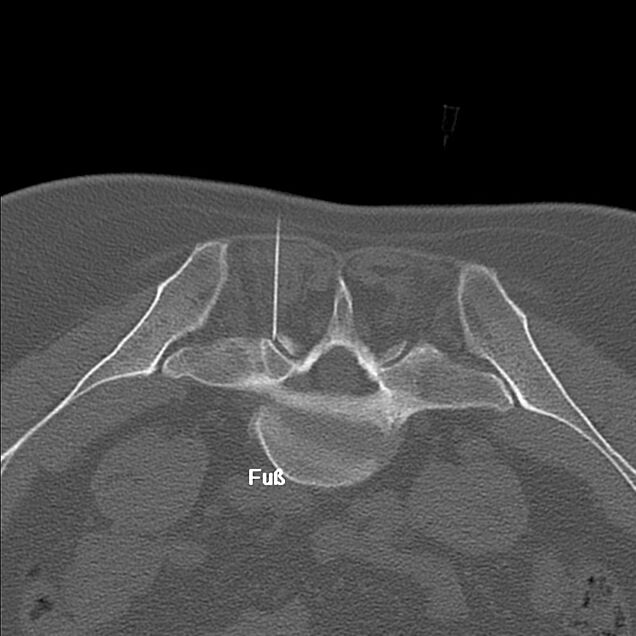

Bei einem isolierten Bandscheibenvorfall oder Aktivierung der Arthrose in 1-2 Facettengelenken kann eine Serie von 4-6 Injektionen von Kortison und Lokalanästhetikum direkt in der Nähe der betroffenen Struktur erfolgen. Dadurch wird die lokale Schwellung und Entzündung gelindert und damit auch die Schmerzbeschwerden. Früher wurden die oben genannten Blockaden mit Hilfe von C-Bogen durchgeführt. Aktuell stellen CT gesteuerte Blockaden eine deutlich bessere Alternative dar – vor allem das Risiko von Komplikationen wie Verletzung der Nervenwurzel kann signifikant reduziert werden. Diese Eingriffe werden im Medical Center Baden-Baden in der Gemeinschaftspraxis: Radiologie Baden-Baden durchgeführt.